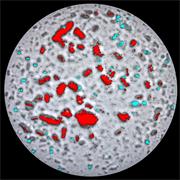

- Generate images of the formulations used in tablets, inhalers and nasal sprays at sub-micrometre spatial resolution

- Fast, quantitative analyses of entire tablets and powder blends

- Determine the uniformity of mixing

- Identify contaminants

Rapidly generate images of your formulations with StreamLine™. This uses line focus illumination, allowing you to use higher laser powers without risk of sample damage, thereby reducing experiment times.

With the RA802 pharmaceutical analyser you can achieve imaging speeds of over 1500 spectra/s. It takes less than 2 minutes, from placing a standard tablet in the system, to generate a full, high resolution Raman image.

Generate images of formulations

Ensure your chemical images are representative; use Renishaw's StreamLine. You can change resolution to suit your domain size and, because Renishaw's WiRE software can cope with massive data files, you can analyse over the entire sample surface. Powerful Renishaw features, such as Slalom (to ensure the whole surface is sampled) and HD imaging (to get crisp clear images), provide all the options you need, whatever your formulation.